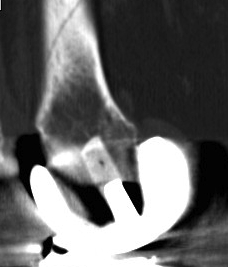

TKR Periprosthetic Fracture Minimall Dislplaced CTTKR Periprosthetic Fracture Locking Plate APTKR Periprosthetic Fracture Locking Plate Lateral

Complications

Non union

Periprosthetic Locking Plate NonunionPeriprosthetic TKR Locking Plate Nonunion 2Periprosthetic TKR Locking Plate Nonunion 30001Periprosthetic TKR Locking Plate Nonunion 30002

Periprosthetic TKR Locking Plate Nonunion 5Periprosthetic TKR Locking Plate Nonunion 6